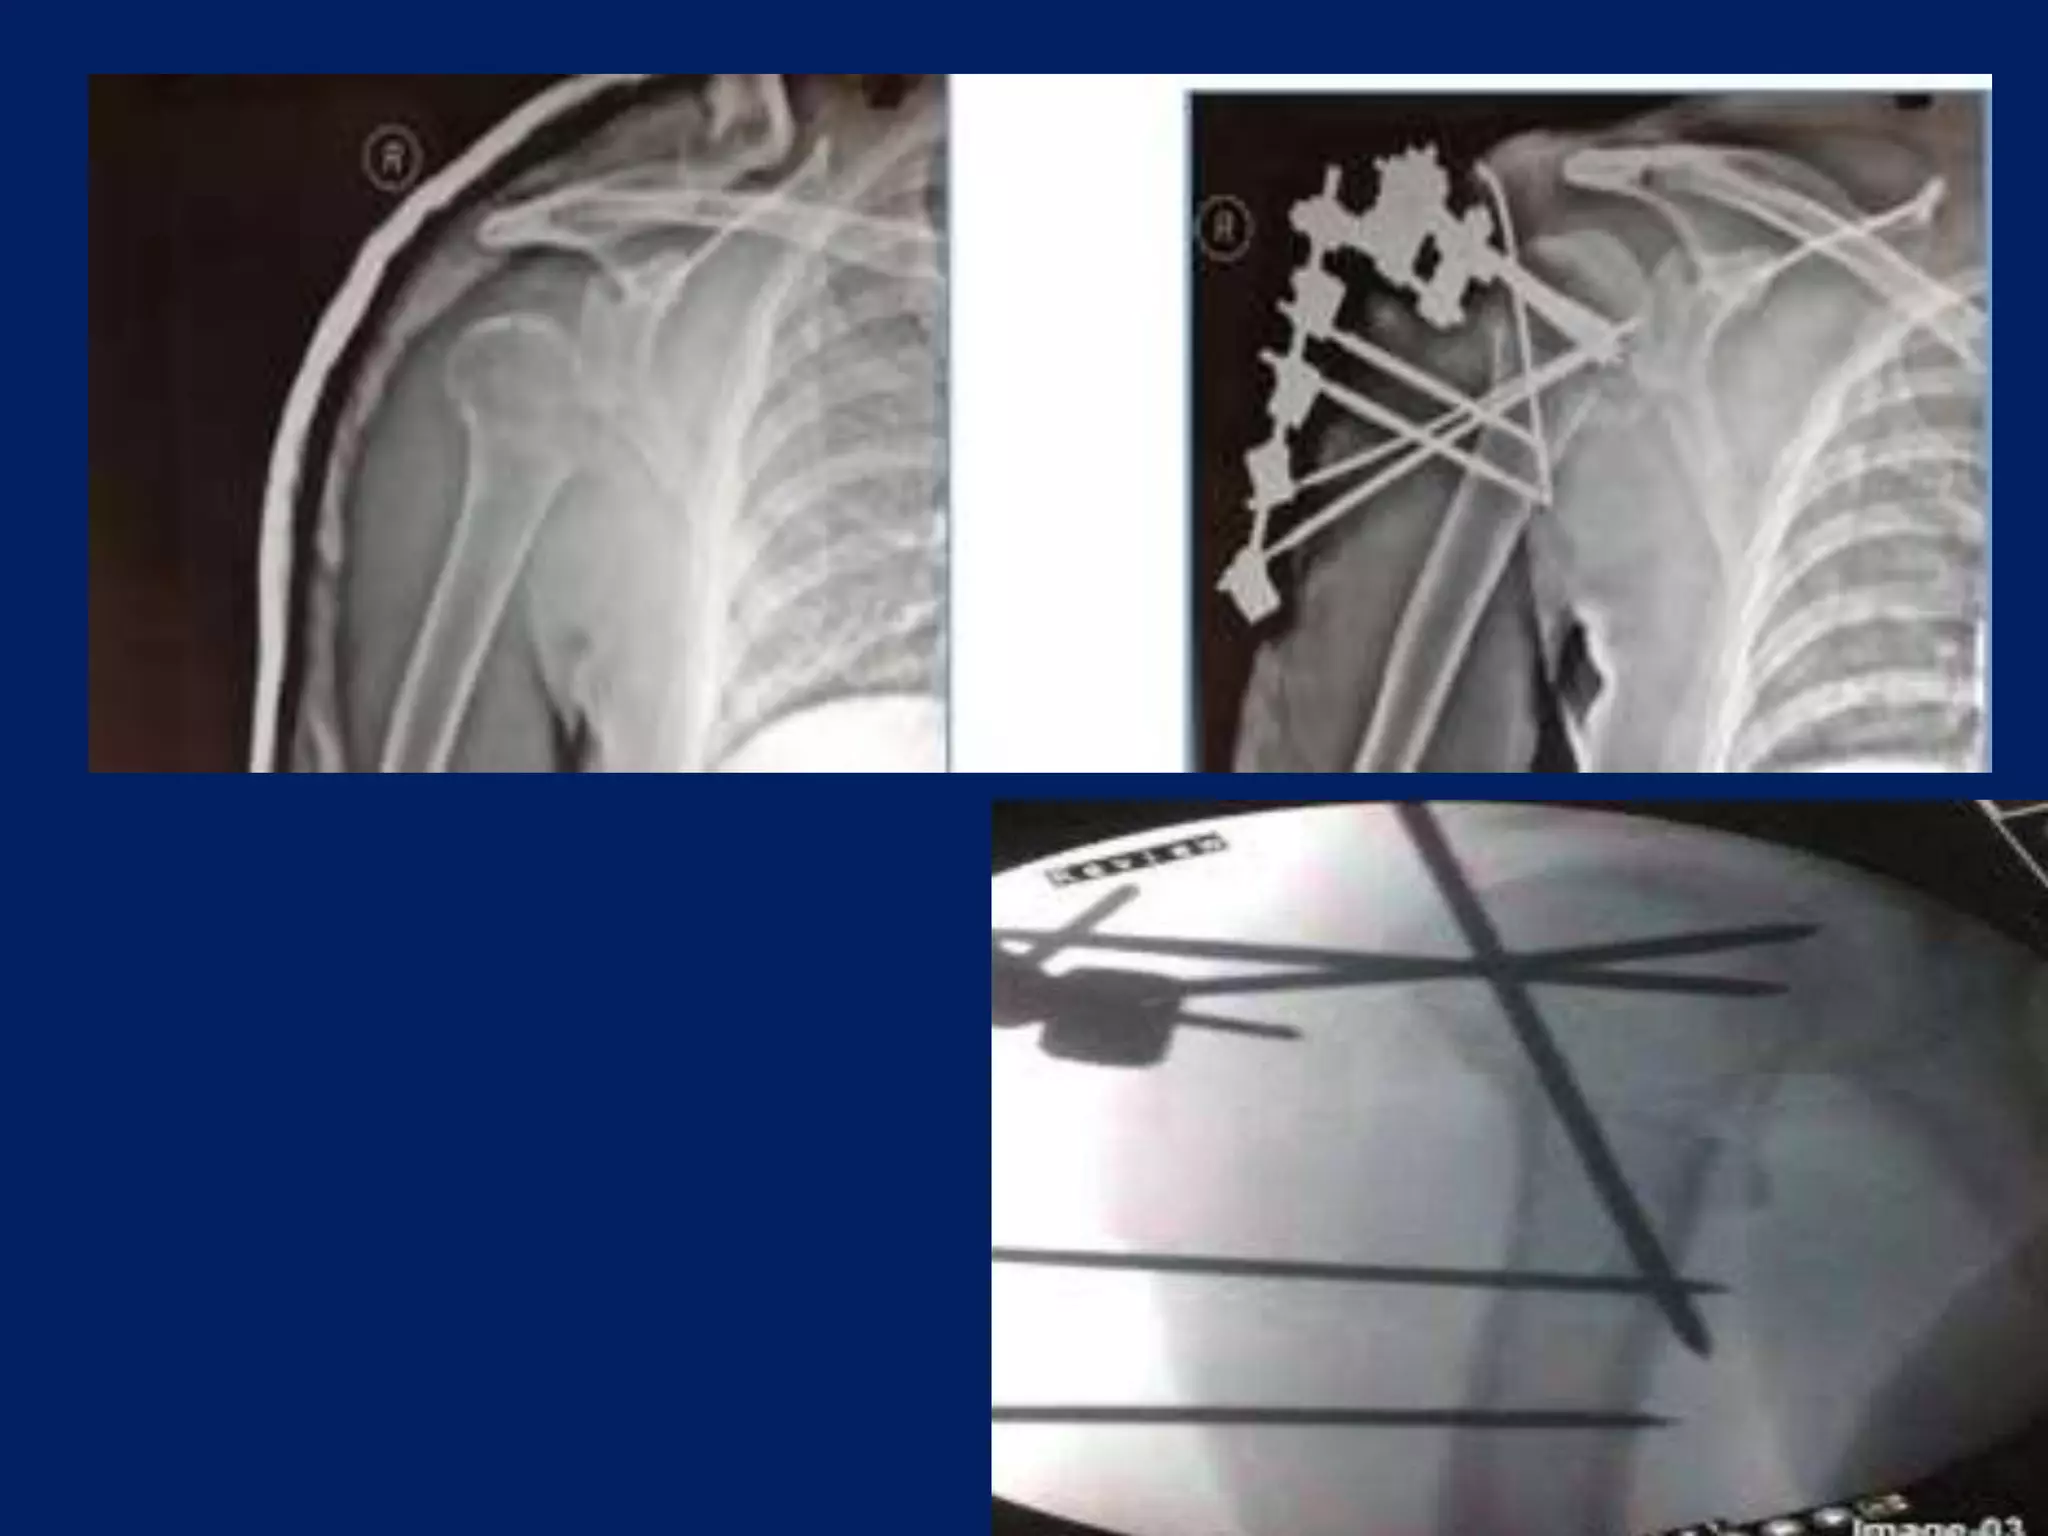

Fracture proximal humerus Fixation with K wires and External fixator

Operative contd... • 2.5mmSchanz pins/ K wire at humeral head at 300 to each other in horizontal plane. • 1st: In true lateral/ coronal plane 2nd: just lateral to bicipital groove 3rd: 300 posterior to 1st one.

• Next 2.5mmpin inserted in coronal plane in line with 1st pin, approximately 4cm or 3 finger/ below the 1st pin in upper third of Humerus. • 3rd pin placed 2cm below the above pin laterally. • Wires are placed from lateral cortex to medial cortex into the head upto the subchondral area